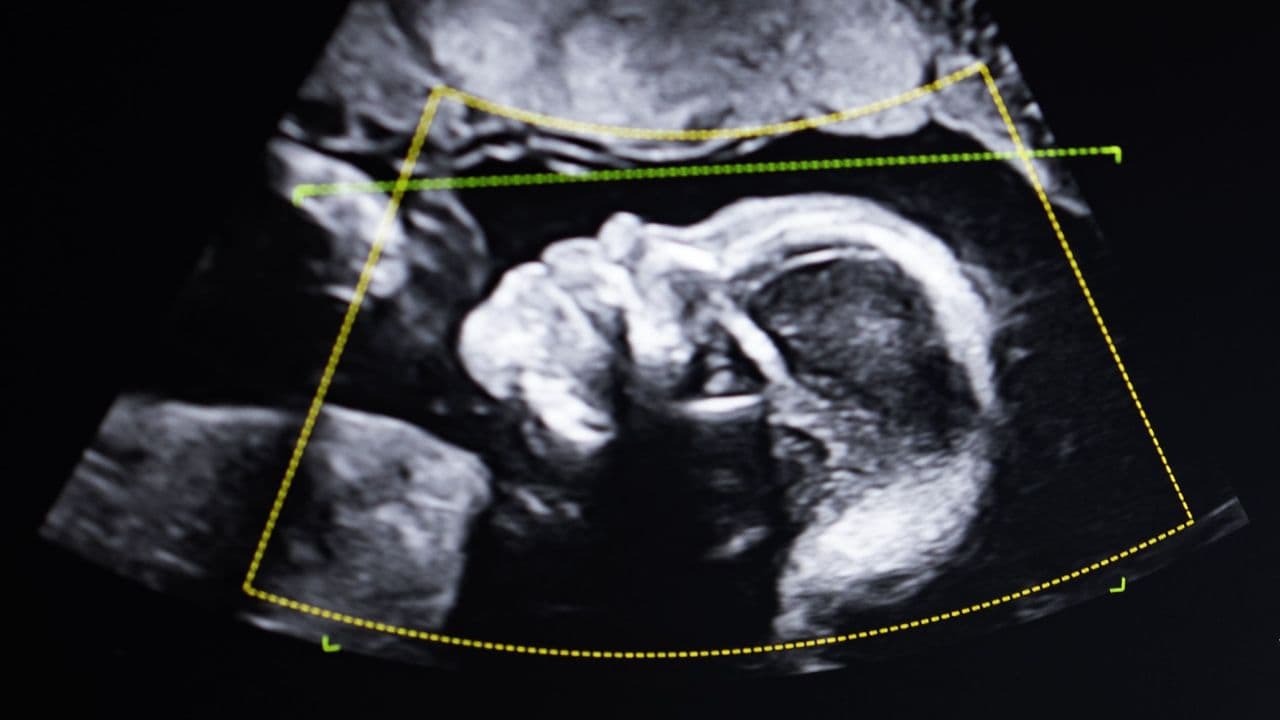

'It doesn't lie. So who are you?': What happens when DNA tests show a woman is not the mother of the child she gave birth to?

"At first, I kind of laughed … But they were serious. I could just see the seriousness in their faces." In this book excerpt, Lise Barnéoud explores the limitations of DNA testing.